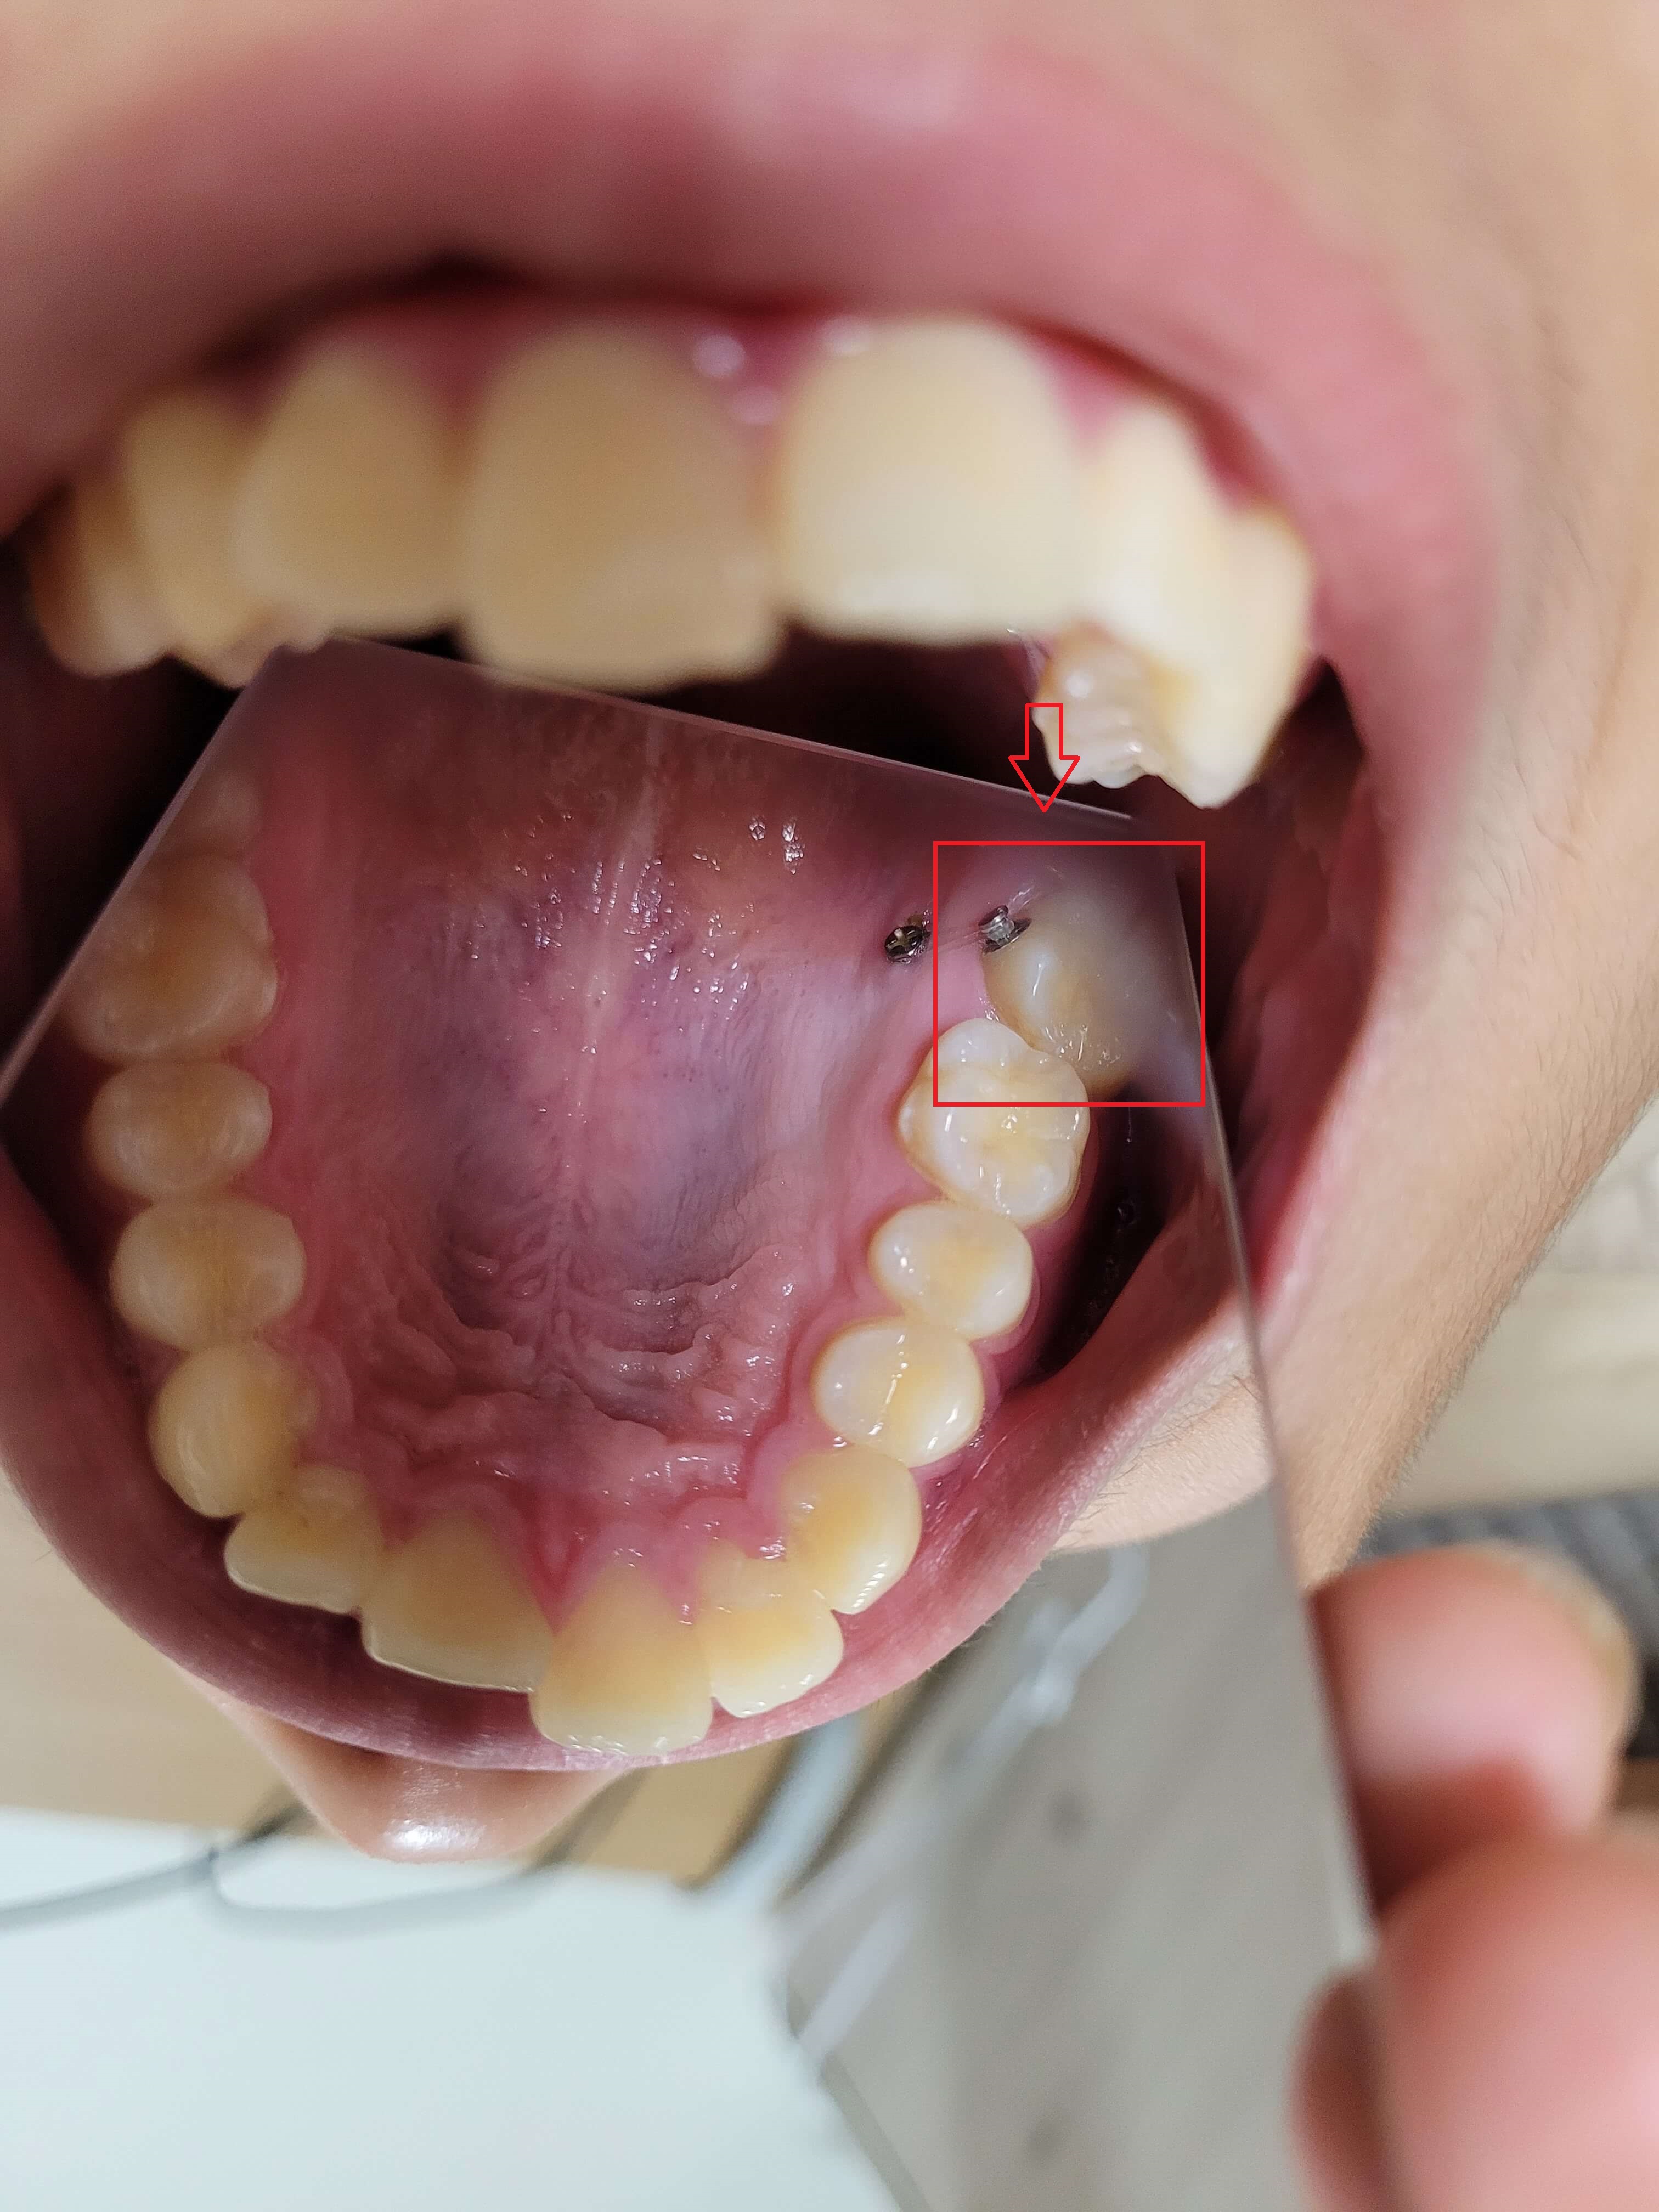

■ 정밀검사 2차 (5개월차)

전체 교정 브라켓을 부착 후 2달 정도 지나고 나니 S자로 휘어진 철사가 어느 정도 일자로 복원되면서 앞니의 치아배열이 가지런하게 정리가 되어있습니다.

이제부터 본격적인 장기레이스 정밀하게 교정에 들어가기 위해 2차 정밀 검사를 하게 되는데요. 좀 더 미관적으로 기능적으로 좋은 치료 방향을 잡기 검사를 하였습니다.

검사결과 발치여부의 선택이 있었고 발치를 하면 약간 튀어나온 입이 좀 더 보기 좋게 들어갈 수 있고 발치를 하지 않아도 크게 문제가 되지 않는다고 하였습니다.

발치로 인해 얻는 효과가 크지 않아 비발치로 선택하고 본격적인 교정에 들어갔습니다.

교정 진행과정은 순조롭게 진행이 잘되었으며 전체 교정기간 5개월 정도 지난 후 상태를 확인하였고 발치 후 교정, 비발치 교정의 선택만 하면 되었습니다.

위, 아래 발치 2개씩을 하면 치아공간이 생겨 좀 더 나은 교정이 될 수 있지만 비발치를 하여도 크게 문제가 되지 않기에 비발치를 선택하였습니다.

▼ 5개월 교정 후 사진(1)

▼ 5개월 교정후 사진(2)